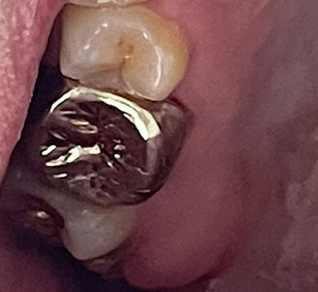

이후로 자세히 안 보고 살았는데 현재 모습입니다. 좀 누르스름 하긴 하지만 치석은 크게 쌓인 거 같지는 않네요.

저도 말로만 듣던 금니라는 걸 껴 보았습니다. 예전엔 이빨이 통째로 금이라서 금니인가 했는데 크라운 방식으로 씌우는 것이더군요. 처음에는 뭔가 이가 꽉 안 다물어지는 느낌이 들었었는데 의사 선생님 말씀처럼 시간이 점점 지나면서 적응이 되더군요. 1년이 지난 지금은 아주 잘 적응해서 이질감이 전혀 안 느껴집니다.